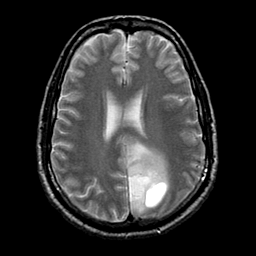

glioma overlay -- Slice #18

[Home][Help][Clinical] Slice 18